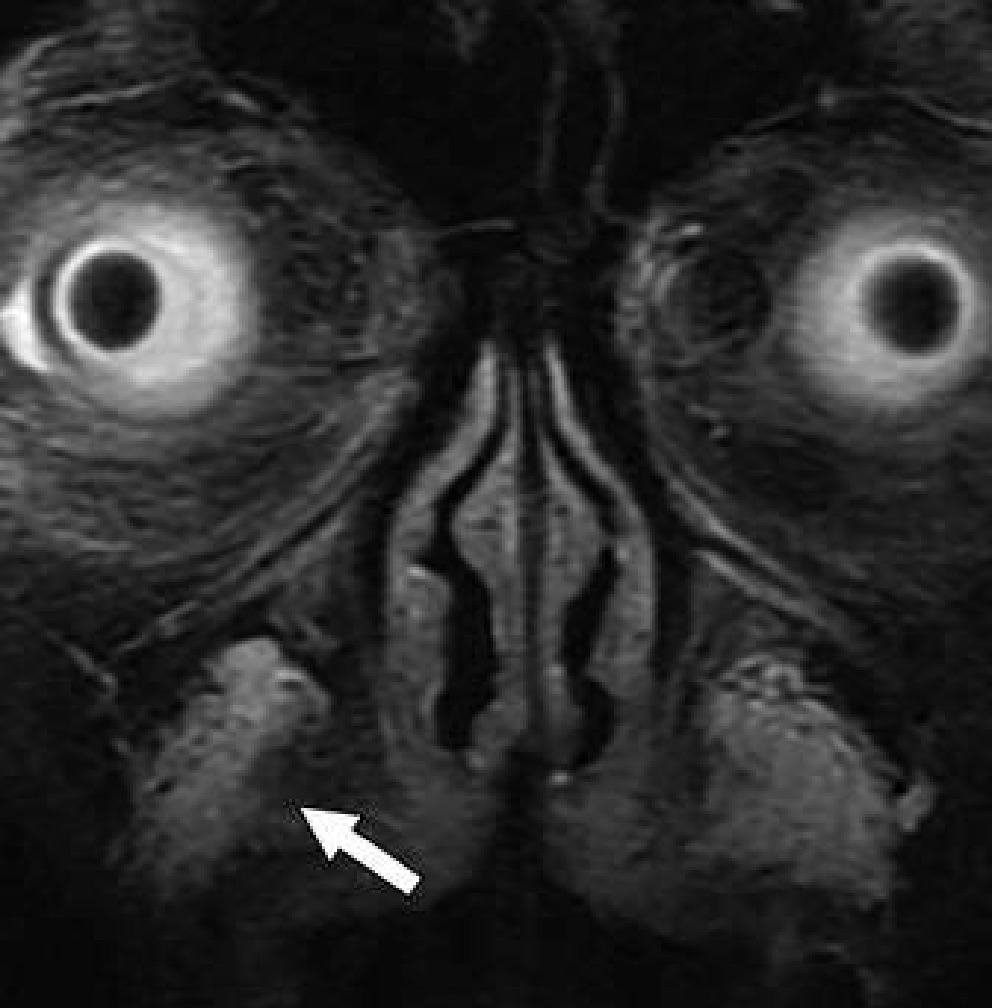

When evaluating urethral complications from phalloplasty in trans-males, because the neo-to-native urethra anastomosis site will evidence diameter differences, retrograde urethrograms can result in stricture overdiagnosis. Apropos, preliminary assessments should be for functional stricture, alongside the performance of urodynamic studies. “However,” noted Doo, “for confirmation of stricture with abnormal function tests and also for evaluation for fistula, a retrograde urethrogram or voiding cystourethrogram can be obtained.” Should a patient desire erectile potential with the fully-healed neophallus, an implant may be placed, which is prone to infection, attrition, malposition and constituent separation (Fig. 2).

Fig. 2 — Scout image from contrast-enhanced CT shows erectile implant; stainless steel and silicone anchors (arrow) transfixed to pubic bone are asymmetric.